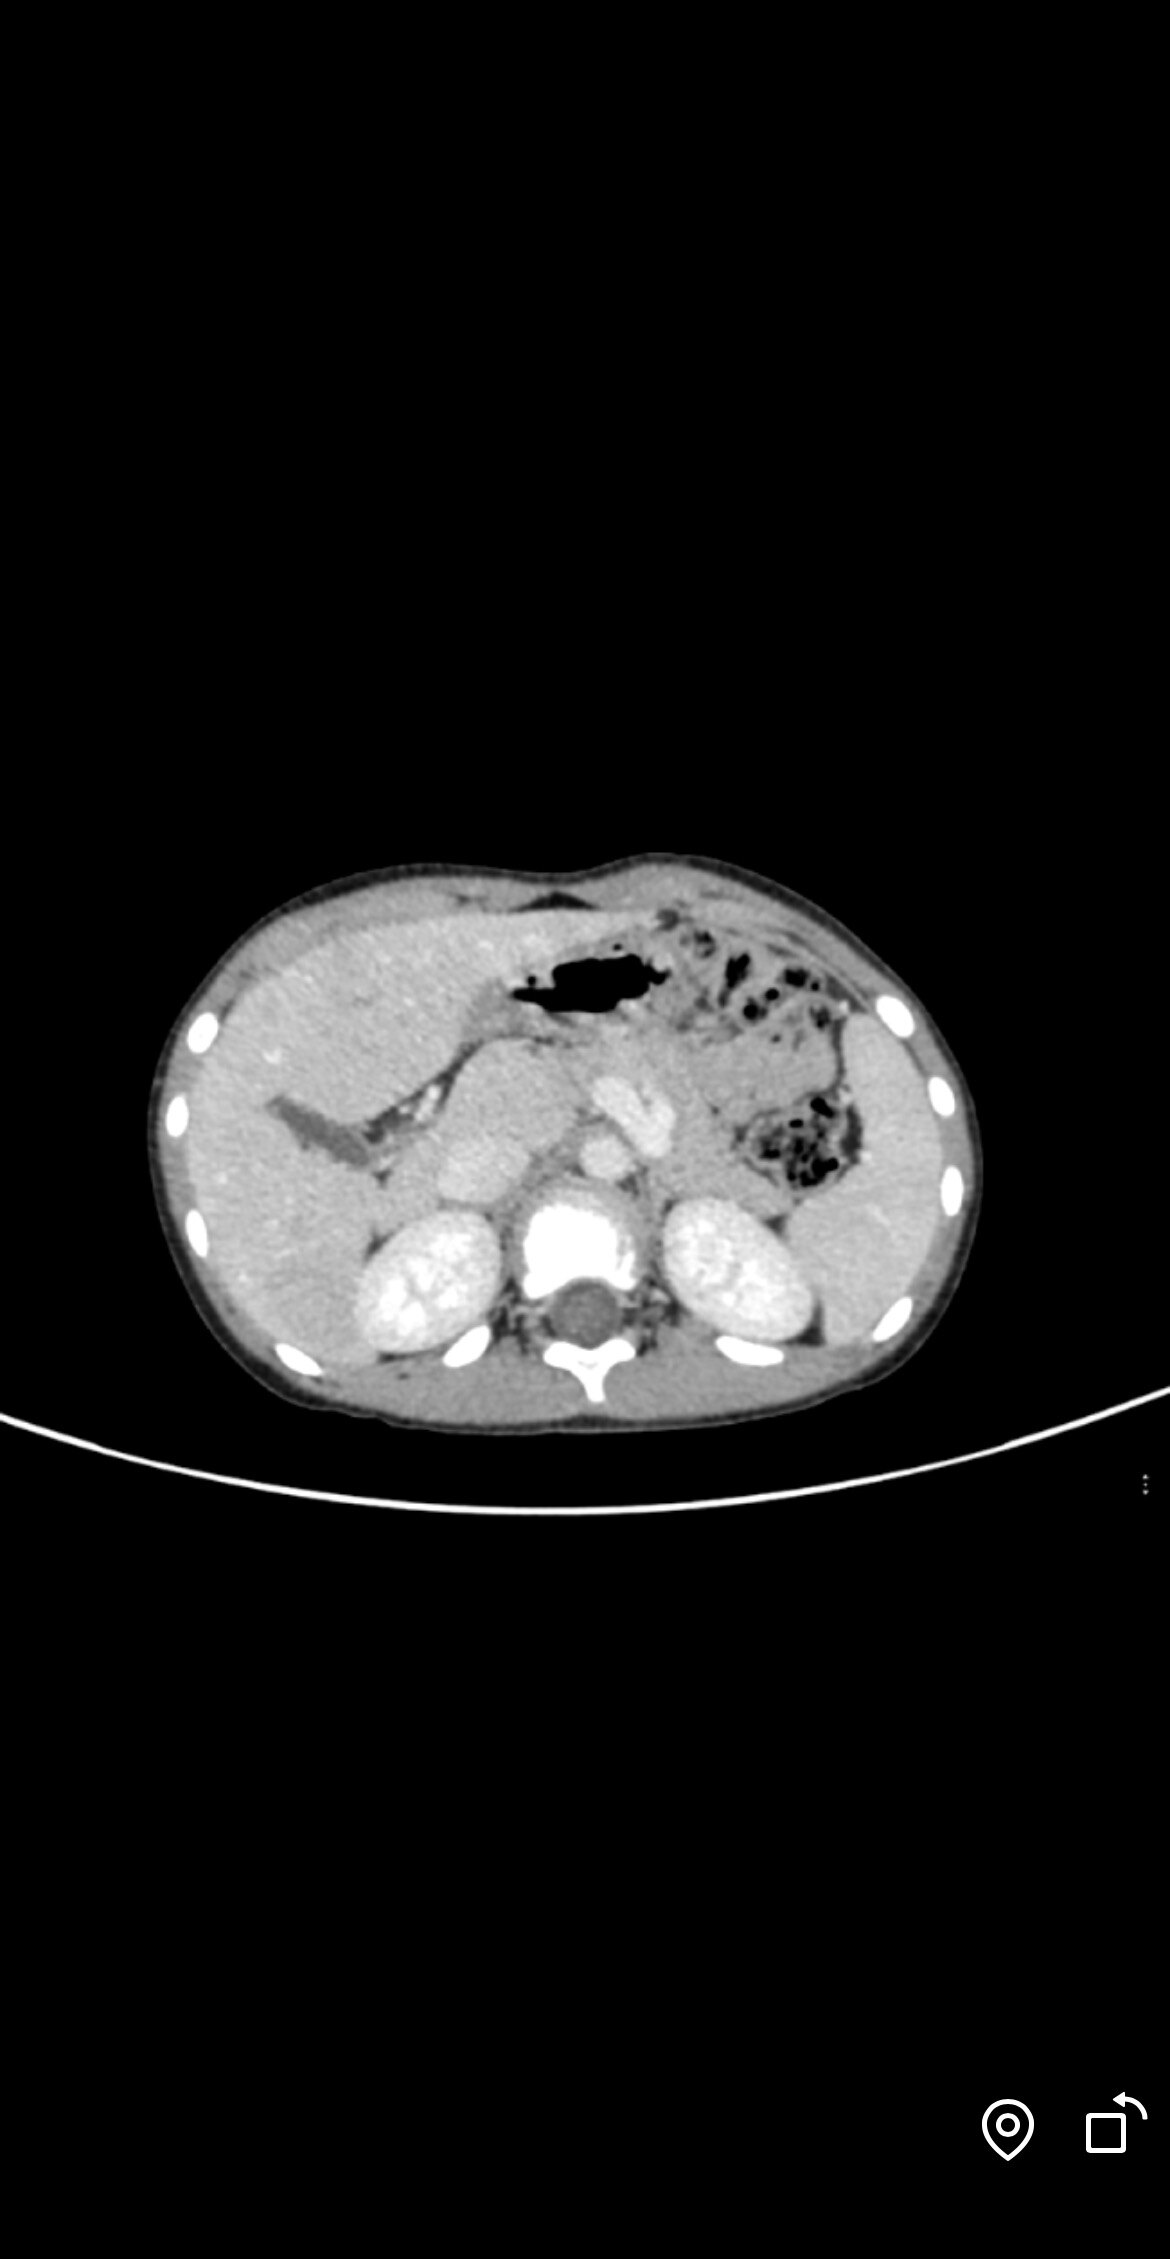

什么是Abernethy畸形?Abernethy畸形,也稱為先天性肝外門(mén)腔靜脈分流(CEPS),是一種罕見(jiàn)的肝臟血管畸形疾病。這種病癥指的是部分或全部的內(nèi)臟靜脈血液通過(guò)先天異常的分流道繞過(guò)肝臟直接回流至體循環(huán)靜脈。全球報(bào)道的病例不超過(guò)703例,國(guó)內(nèi)報(bào)道的病例有82例。Abernethy綜合征通常發(fā)生在兒童和青少年身上,尤其是在18歲以下的年齡段。根據(jù)一項(xiàng)綜合分析了2001年至2012年中國(guó)報(bào)道的18例Abernethy畸形患者的研究,Ⅰ型患者中92%的發(fā)病年齡在18歲以下,確診年齡中85%也在18歲以下。另一項(xiàng)研究分析了380例患者資料,其中Ⅰ型患者平均年齡為17.08歲,Ⅱ型患者平均年齡為14.85歲。這些數(shù)據(jù)表明,Aberneth畸形多見(jiàn)于兒童和青少年,但也可以在成年早期發(fā)現(xiàn)。分型Abernethy畸形分為兩個(gè)類(lèi)型:I型:也稱為先天性門(mén)靜脈缺失(CAPV),肝內(nèi)門(mén)靜脈分支缺失,門(mén)靜脈血完全分流至全身靜脈(下腔靜脈、腎靜脈或髂靜脈)。進(jìn)一步分為Ia型和Ib型,Ia型中腸系膜上靜脈和脾靜脈分別引流至體靜脈,而Ib型中腸系膜上靜脈和脾靜脈匯合形成短的肝外門(mén)靜脈,流入全身靜脈。II型:為側(cè)-側(cè)分流,門(mén)靜脈發(fā)育不良,門(mén)靜脈血部分向肝臟灌注,肝外門(mén)腔靜脈間存在先天性分流,肝內(nèi)門(mén)靜脈完整。臨床表現(xiàn)Abernethy畸形的患者可能會(huì)出現(xiàn)不同程度的肝功能受損表現(xiàn),如消化不良、黃疸、出血貧血等。分流血管代償性擴(kuò)張并破裂可能造成嘔血、便血、痔瘡出血等。多數(shù)患者以并發(fā)癥為首發(fā)癥狀就醫(yī)。此外,患者還可能出現(xiàn)以下表現(xiàn):肝臟結(jié)節(jié):少許肝結(jié)節(jié)可發(fā)展成為腫瘤。肝性腦病:發(fā)生率約為15%,多呈慢性且輕癥,表現(xiàn)為心理智力測(cè)試輕度異常、持續(xù)認(rèn)知功能障礙及行為異常。合并癥Abernethy畸形可發(fā)生嚴(yán)重的合并癥,包括新生兒膽汁淤積、良性和惡性肝臟腫瘤、肝肺綜合征、肺動(dòng)脈高壓和肝性腦病。在我們團(tuán)隊(duì)接診的患兒中,有占比不少的肝外癥狀為首發(fā)表現(xiàn)。治療治療方案根據(jù)Abernethy畸形不同類(lèi)型及病人情況決定。主要有:內(nèi)科保守治療:主要是保護(hù)肝功能和治療肝性腦病的方法;阻斷分流道:可減少門(mén)、腔靜脈分流,增加肝門(mén)靜脈血灌注,但可使門(mén)靜脈壓增高。適合于II型患者;脾動(dòng)脈大部分栓塞術(shù):術(shù)后可改善脾大和脾功能亢進(jìn);肝移植:適合于I型患者;尤其是那些伴有嚴(yán)重肝性腦病、肝肺綜合征、肺動(dòng)脈高壓、心力衰竭、肝臟腫瘤或腫瘤樣改變的患者。Abernethy畸形是一種罕見(jiàn)且復(fù)雜的疾病,需要多學(xué)科合作進(jìn)行綜合治療。隨著對(duì)疾病的認(rèn)識(shí)加深,治療方法也在不斷進(jìn)步,為患者提供了更多的治療選擇和希望,也有越多越多的報(bào)道支持早期介入治療能改善預(yù)后。